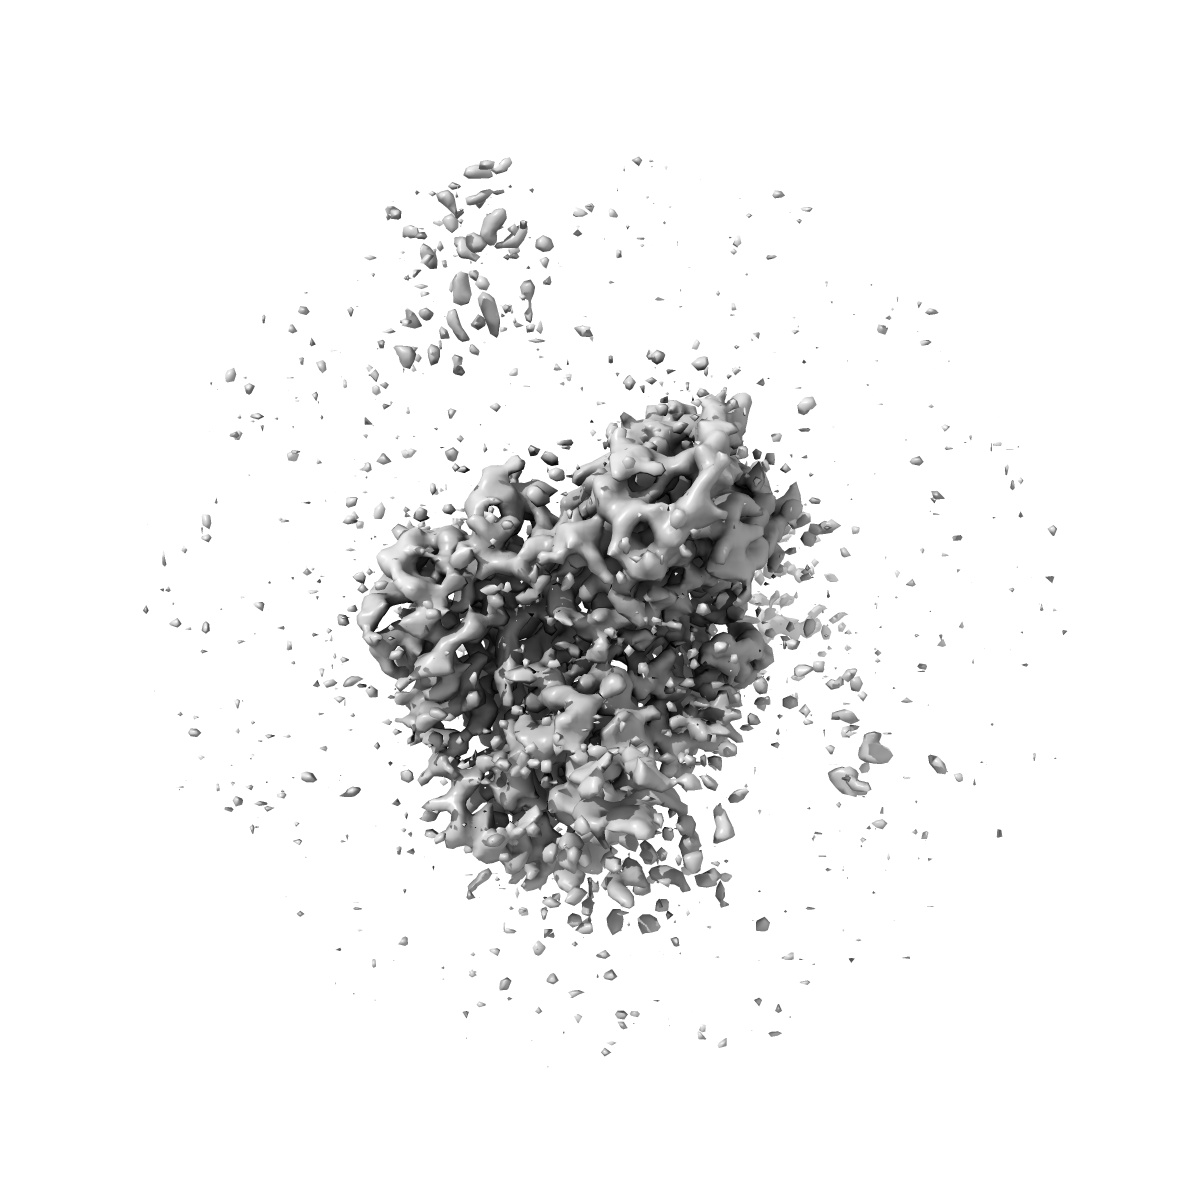

Rapid screening cryo-EM map of CAK bound to ICEC0510-S (grid VC7-4, 1hr collection)

Single-particle3.4 Å

Sample: CDK-activating kinase